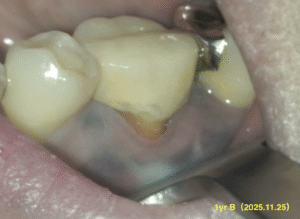

#19 M,D Apicoectomy 1yr recall(2025.11.25)

Sinus tractは

B,Lともに消失した。